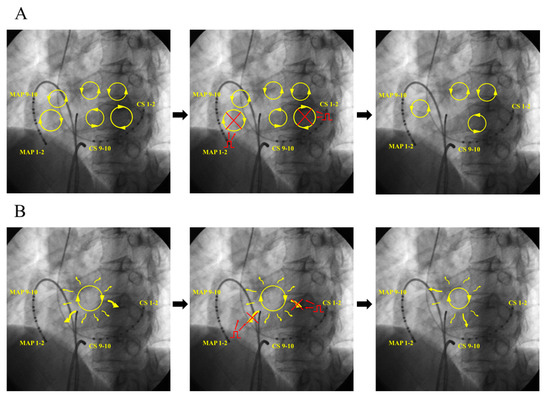

3.2.1. Case 1: 42-Year-Old Man with Symptomatic PAF

3.2.2. Case 2: 72-Year-Old Man with Symptomatic PAF

3.2.3. Case 3: 67-Year-Old Man with Symptomatic PAF

4.1. Mechanism of AF Termination

- (A)

- (B)

- (C)

- Leading circle theory [14]; The presence of an excitable gap is well known for the maintenance of AF. Pacing stimuli entrain and fill the excitable gaps of tachycardia, affecting the refractory period. Eventually, AF is unable to sustain itself and thus terminates slowly.